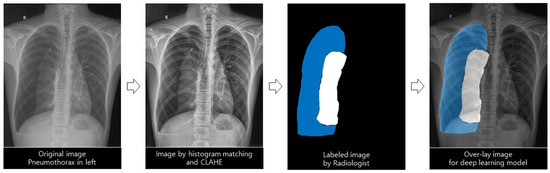

2.3.1. Deep Learning Architecture with the Images Preprocessing Method